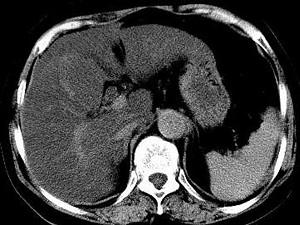

问题 男,32岁,肥胖,常酗酒,肝肋下一横指,肝区轻微压痛,影像表现如图,应诊断为 ( )

选项 A、肝豆状核变性 B、肝含铁血黄素沉着 C、肝硬化 D、脂肪肝 E、肝炎

答案 D